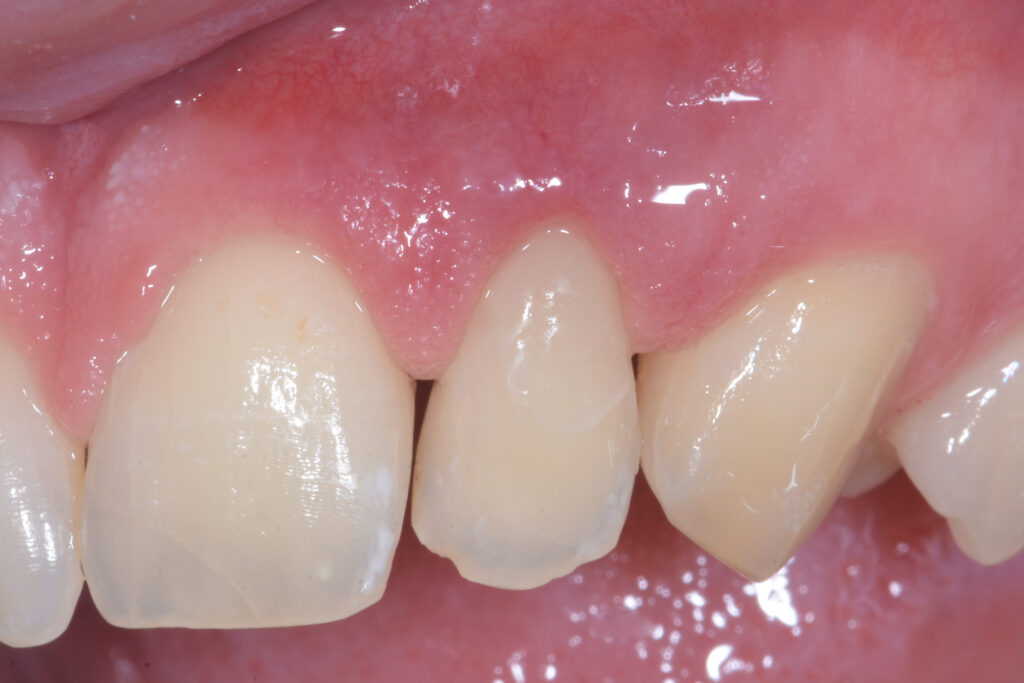

Il paziente si rivolge alla nostra attenzione lamentando un lieve inestetismo a carico dell’elemento 22 (Figura 1). Dopo la diagnosi, in questo caso prettamente clinica essendo la lesione vestibolare, viene proposto il trattamento congiunto chirurgico-conservativo come primo approccio, con l’obiettivo di mantenere per quanto possibile la vitalità dell’elemento dentale.

A due settimane dall’intervento, il paziente riferisce una sintomatologia, lieve e concentrata nelle 48 successive, imputabile alla ferita; la guarigione è ottimale e vengono rimosse le suture (Figura 7). Non sono insorte algie dentali né spontanee né esacerbate dalla stimolazione freddo/caldo. Viene impostato il calendario di follow-up clinico-radiografici con appuntamenti a sei mesi, un anno e due anni.

A distanza di due anni, l’elemento risulta ancora positivo ai test di vitalità e il parodonto è in completa salute (Figura 8). Non è insorta alcuna sintomatologia algica a carico dell’elemento. In ogni caso, si ritiene opportuno mantenere controlli periodici futuri per intercettare possibili recidive.